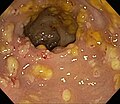

| Endoscopy | pseudomembranes (pale yellow (or white) irregular, raised mucosal lesions), interlesional mucosa often near normal grossly |

Gross

Features:[5]

- Pseudomembranes:

- Pale yellow (or white) irregular, raised mucosal lesions.

- Early lesions: typical <10 mm.

- Interlesional mucosa often near normal grossly.